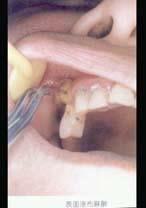

问题 7岁患儿下颌乳中切牙松动Ⅲ度、拔除时宜采用()

选项 A.2%普鲁卡因阻滞麻醉 B.2%利多卡因阻滞麻醉 C.2%普鲁卡因浸润麻醉 D.2%丁卡因表面麻醉 E.2%利多卡因浸润麻醉

答案 D